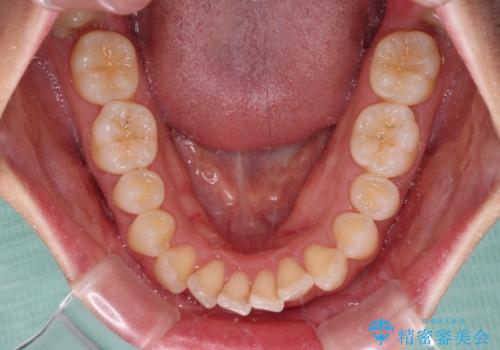

- 上下前歯の隙間と口元の出っ張った感じを気にして来院された患者様です。

上下の隙間は舌突出癖によるもので、またその癖により前歯が前方に出ている状態でした。

口元の出っ張りを改善するため、上下左右第一小臼歯4本を抜去し、ワイヤー装置にて矯正治療を行うこととしました。